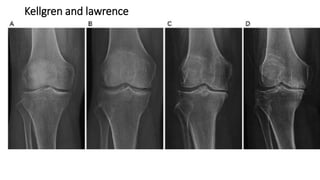

Kellgren and lawrence

• Grade 0 : Normal

• Grade 1: Minimal osteophyte, doubtful significance

• Grade 2: Definite osteophyte, no loss of joint space

• Grade 3: Some diminution of joint space

• Grade 4: Advanced joint space loss and sclerosis of bone